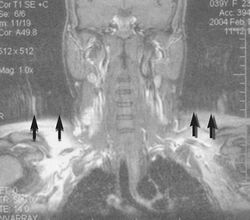

Motion artifact (T1 coronal study of cervical vertebrae)

[137]

An MRI artifact is a visual artifact, that is, an anomaly during visual representation. Many different artifacts can occur during magnetic resonance imaging (MRI), some affecting the diagnostic quality, while others may be confused with pathology. Artifacts can be classified as patient-related, signal processing-dependent and hardware (machine)-related.[137]